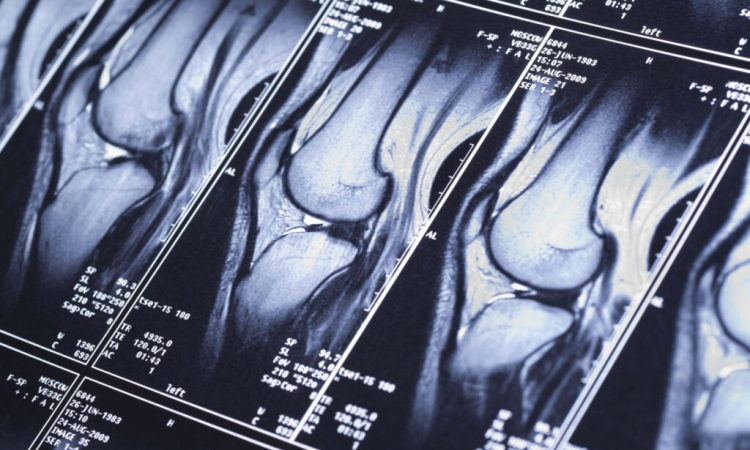

| МРТ коленного сустава | 5 800 |

При наличии заболеваний, подозрениях на них рекомендуется уточнить диагностику. Для этого врачи назначают дополнительное аппаратное обследование. МРТ в Бирюлево проводит специализированный медицинский центр. Метод магнитно-резонансной томографии дает большую эффективность относительно обнаружения нарушений в структурах костей, внутренних органов, мягких тканей. Способ отличает отсутствие волнового облучения. Получение визуальной картины состояния организма осуществляется посредством создания магнитного поля. Патологии внутренних органов обнаруживаются с большой точностью. Врачу предоставляется максимум информации для составления описания болезни, назначения лечения.

Для МРТ используется высокотехнологичное оборудование — томограф. Медицинские центры осуществляют процесс на новейшей аппаратуре с достаточным освещением, возможностью проветривания. Высокая сложность процедуры сочетается с безопасностью для пациента. Получение изображения области поражения на томографе иногда выступает единственным способом установить точный диагноз. На сеансе МРТ Бирюлево обследуемого располагают на подвижном столе, который затем перемещают внутрь магнитного тоннеля аппарата.

Высокая мощность создаваемого устройством магнитного поля направляется на определенную зону тела. Импульсное воздействие встречает отклик атомов водорода, находящихся в тканях организма, воде, частицах жира. Полученные показатели соотносятся с нормой значений здоровых тканей на предмет выявления отклонений. На патологию, ее развитие, степень прогресса указывает количество атомов, не являющееся характерным для исследуемого органа. Резонанс улавливается функциональными элементами конструкции, создается картина состояния области тела. Полученная информация визуализируется с помощью специальной программы. Так специалисты видят изображение среза органа и детализируют подробности на четких снимках.